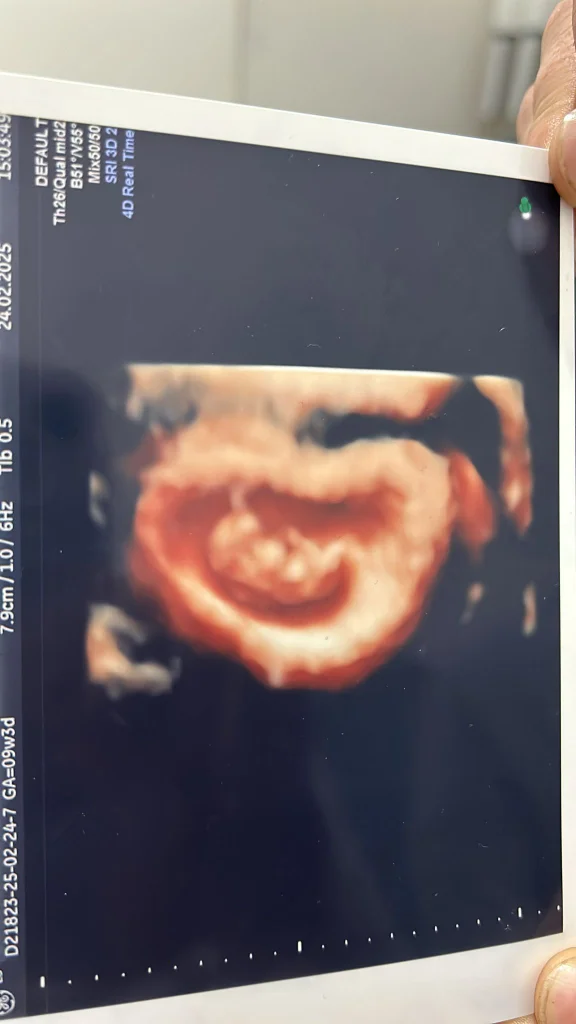

bizde bu gun 9 haftalık olduk

beni tanıyanlar hepsi yanlış düşünmüş ben dahil

Hiç bukadar şaşırmamıştım kız bekliyordum